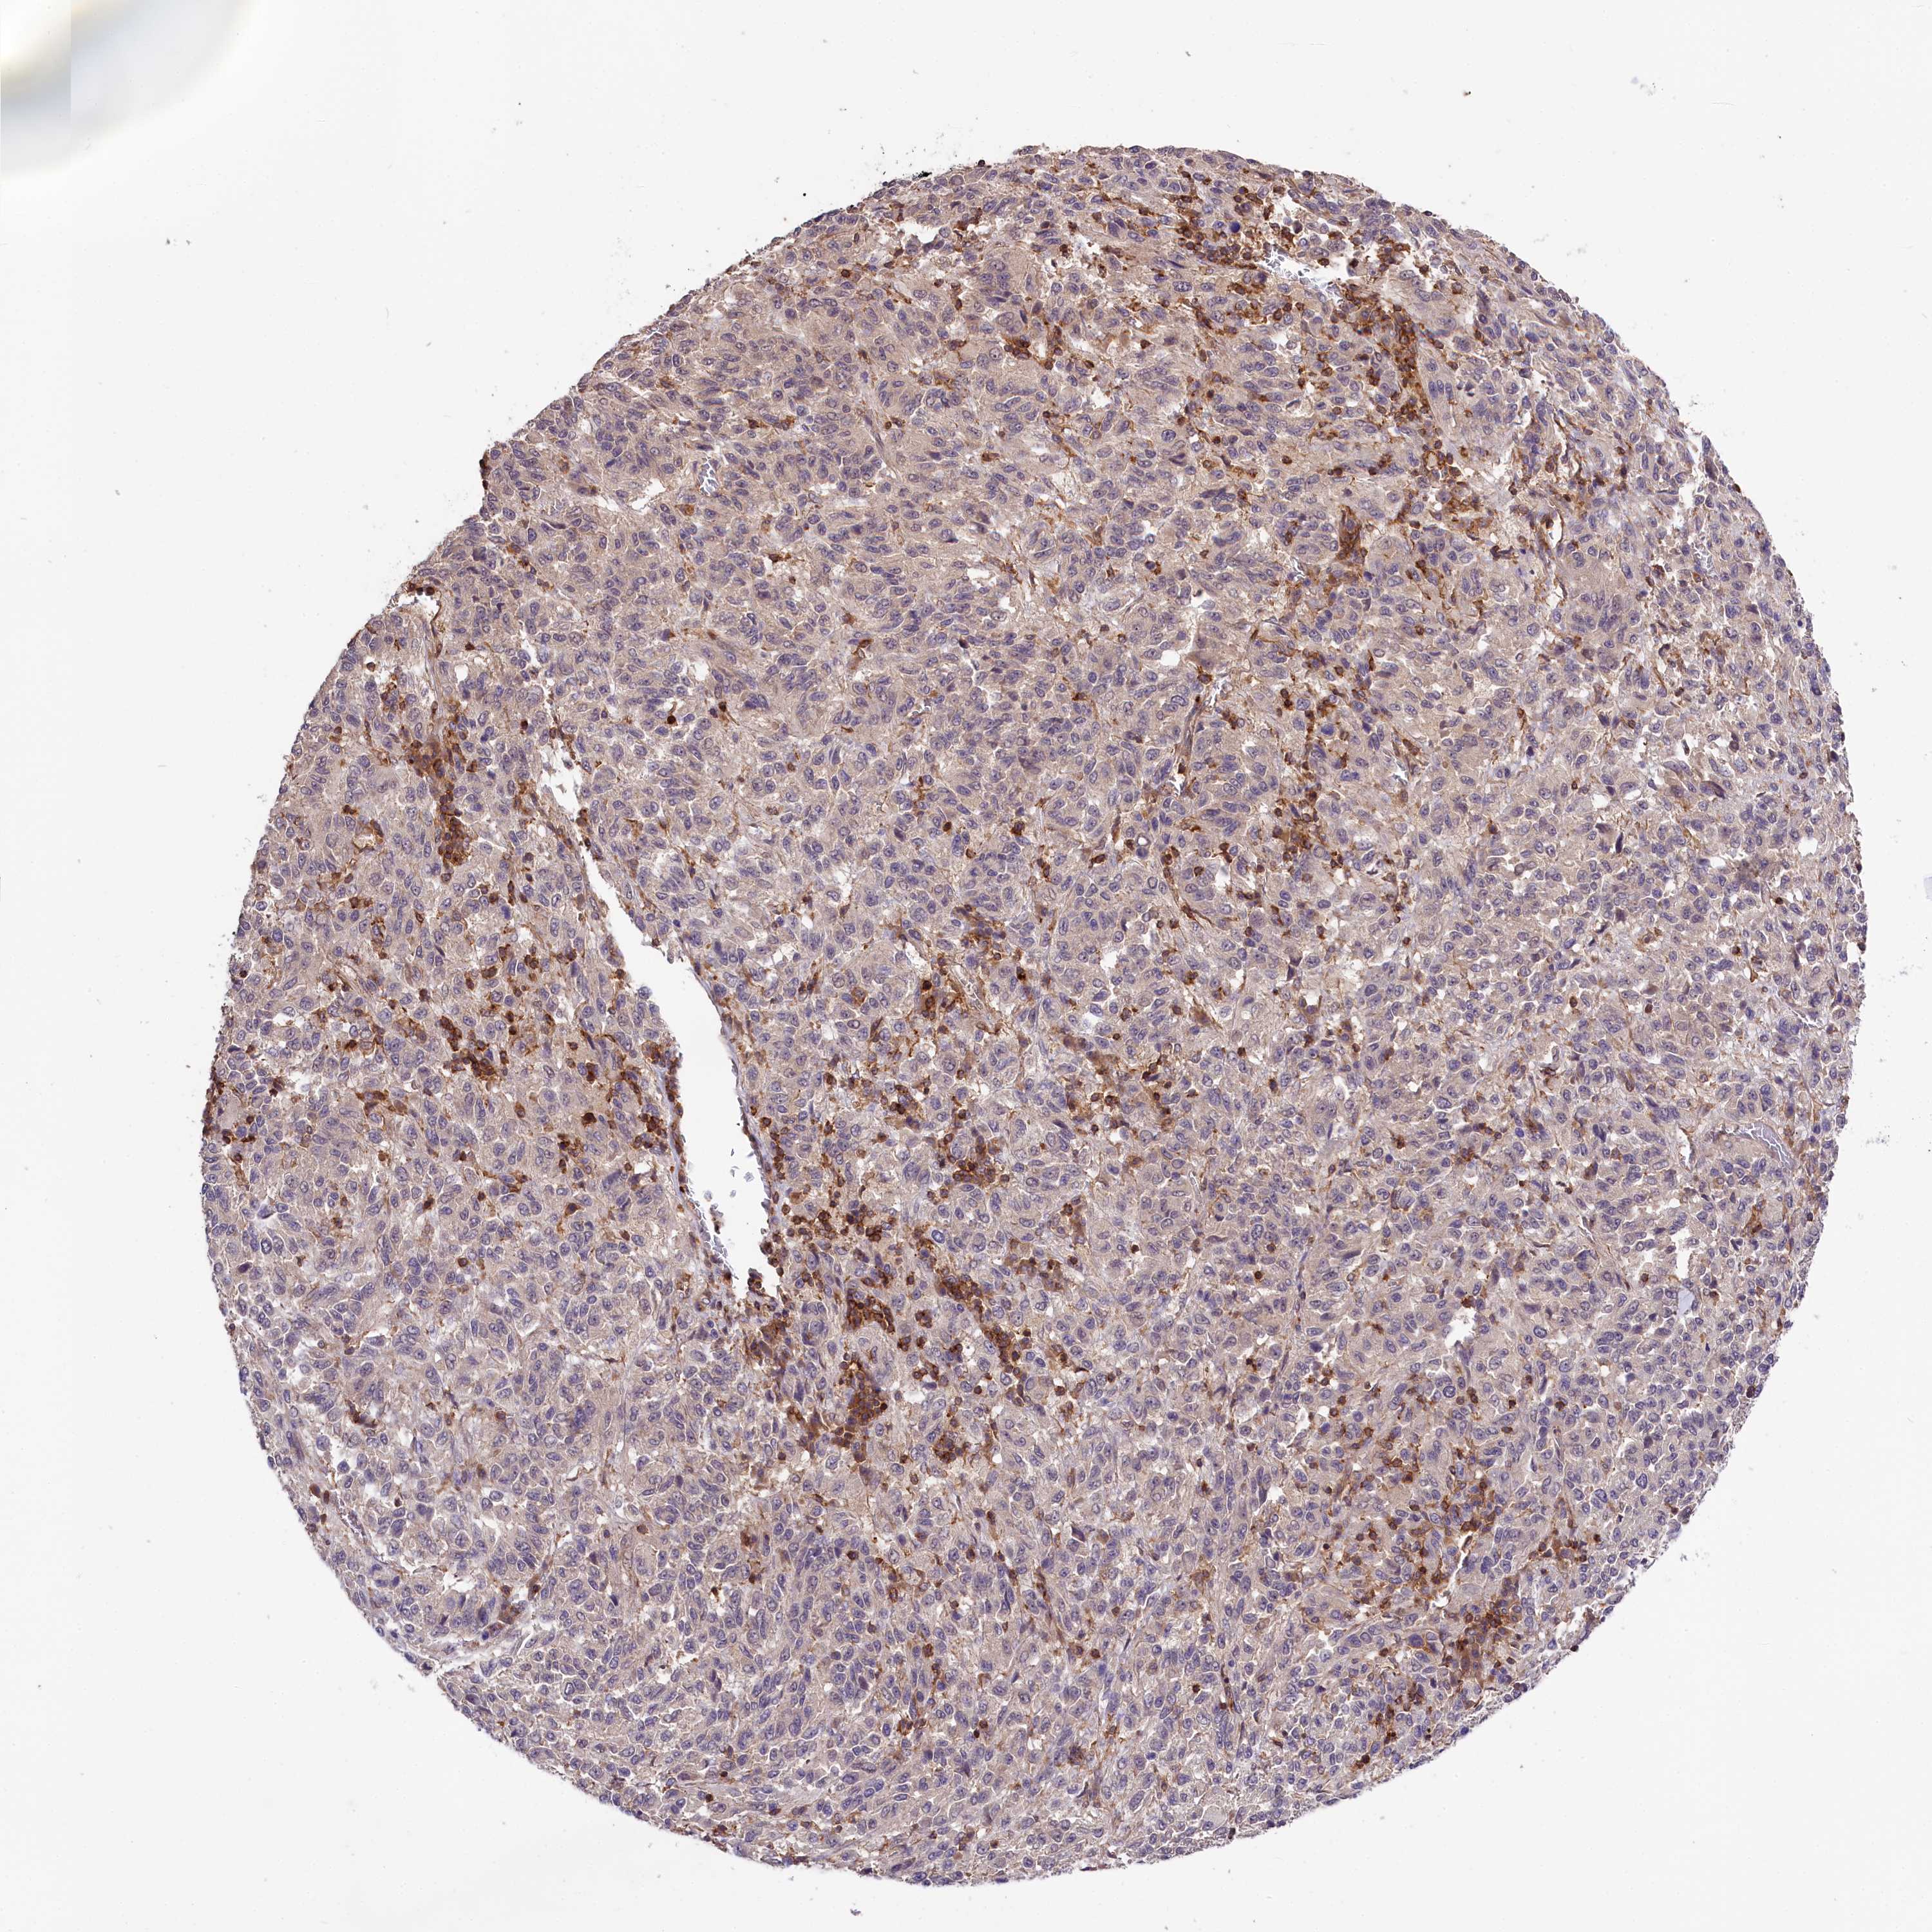

MELANOMA - Protein expressioni

A mouse-over function shows sample information and annotation data. Click on an image to view it in a full screen mode. Samples can be filtered based on level of antibody staining by selecting one or several of the following categories: high, medium, low and not detected. The assay and annotation is described here.

Note that samples used for immunohistochemistry by the Human Protein Atlas do not correspond to samples in the TCGA dataset.

Antibody stainingi

Antibody staining in the annotated cell types in the current human tissue is reported as not detected, low, medium, or high, based on conventional immunohistochemistry profiling in selected tissues. This score is based on the combination of the staining intensity and fraction of stained cells.

Each image is clickable and will lead to virtual microscopy that enables deeper exploration of all samples and also displays staining intensity scores, fraction scores and subcellular localization as well as patient and tissue information for each sample.

Antibody HPA039208

Antibody HPA040439

Staining

High

Medium

Low

Not detected

Intensity

Strong

Moderate

Weak

Negative

Quantity

>75%

75%-25%

<25%

None

Location

Nuclear

Cytoplasmic/membranous

Cytoplasmic/membranous,nuclear

Malignant melanoma, NOS

Malignant melanoma, Metastatic site